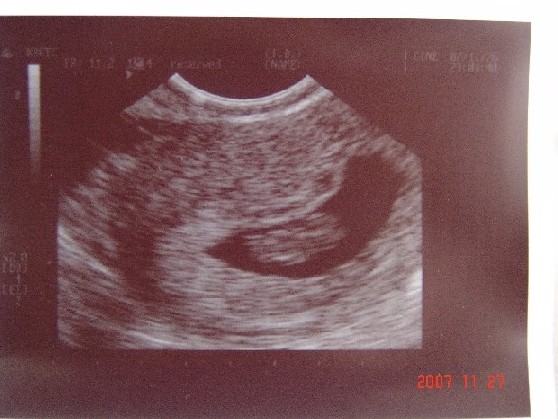

Marietta! Nagyon édes a kis masztkád a képen. Nekem is kb. ennyi látszott az első felvételen.